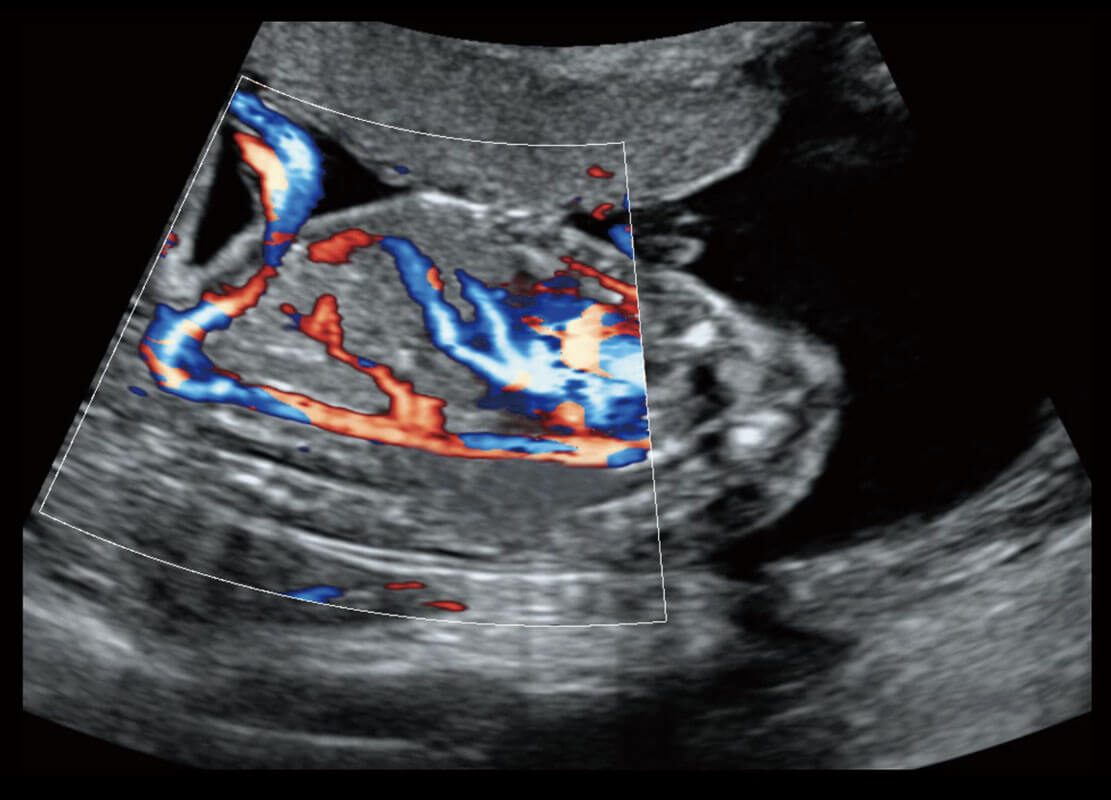

生殖健康

P60优异的图像质量搭载专科探头,在妇科基础疾病的诊断、卵泡生长的监测、输卵管通畅情况的判别等方面为您提供生殖应用方案。

盆底超声

P60为盆底超声检查提供应用方案,多种腔内及腹部容积探头提供从二维、三维到四维的优异图像品质,实时快速三维容积数据获取,专业的测量工具包等人性化设计,为超声医生诊断提供有力保障。